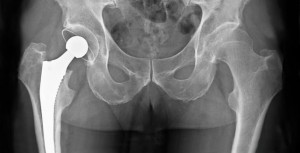

Infección de prótesis articular: qué hacer cuando no se puede operar

06 junio 2017

El tratamiento antibiótico supresor prolongado podría ser eficaz en pacientes ancianos en los que la opción quirúrgica no es una alternativa. European Journal of Clinical Microbiology & Infectious Diseases, abril de 2017